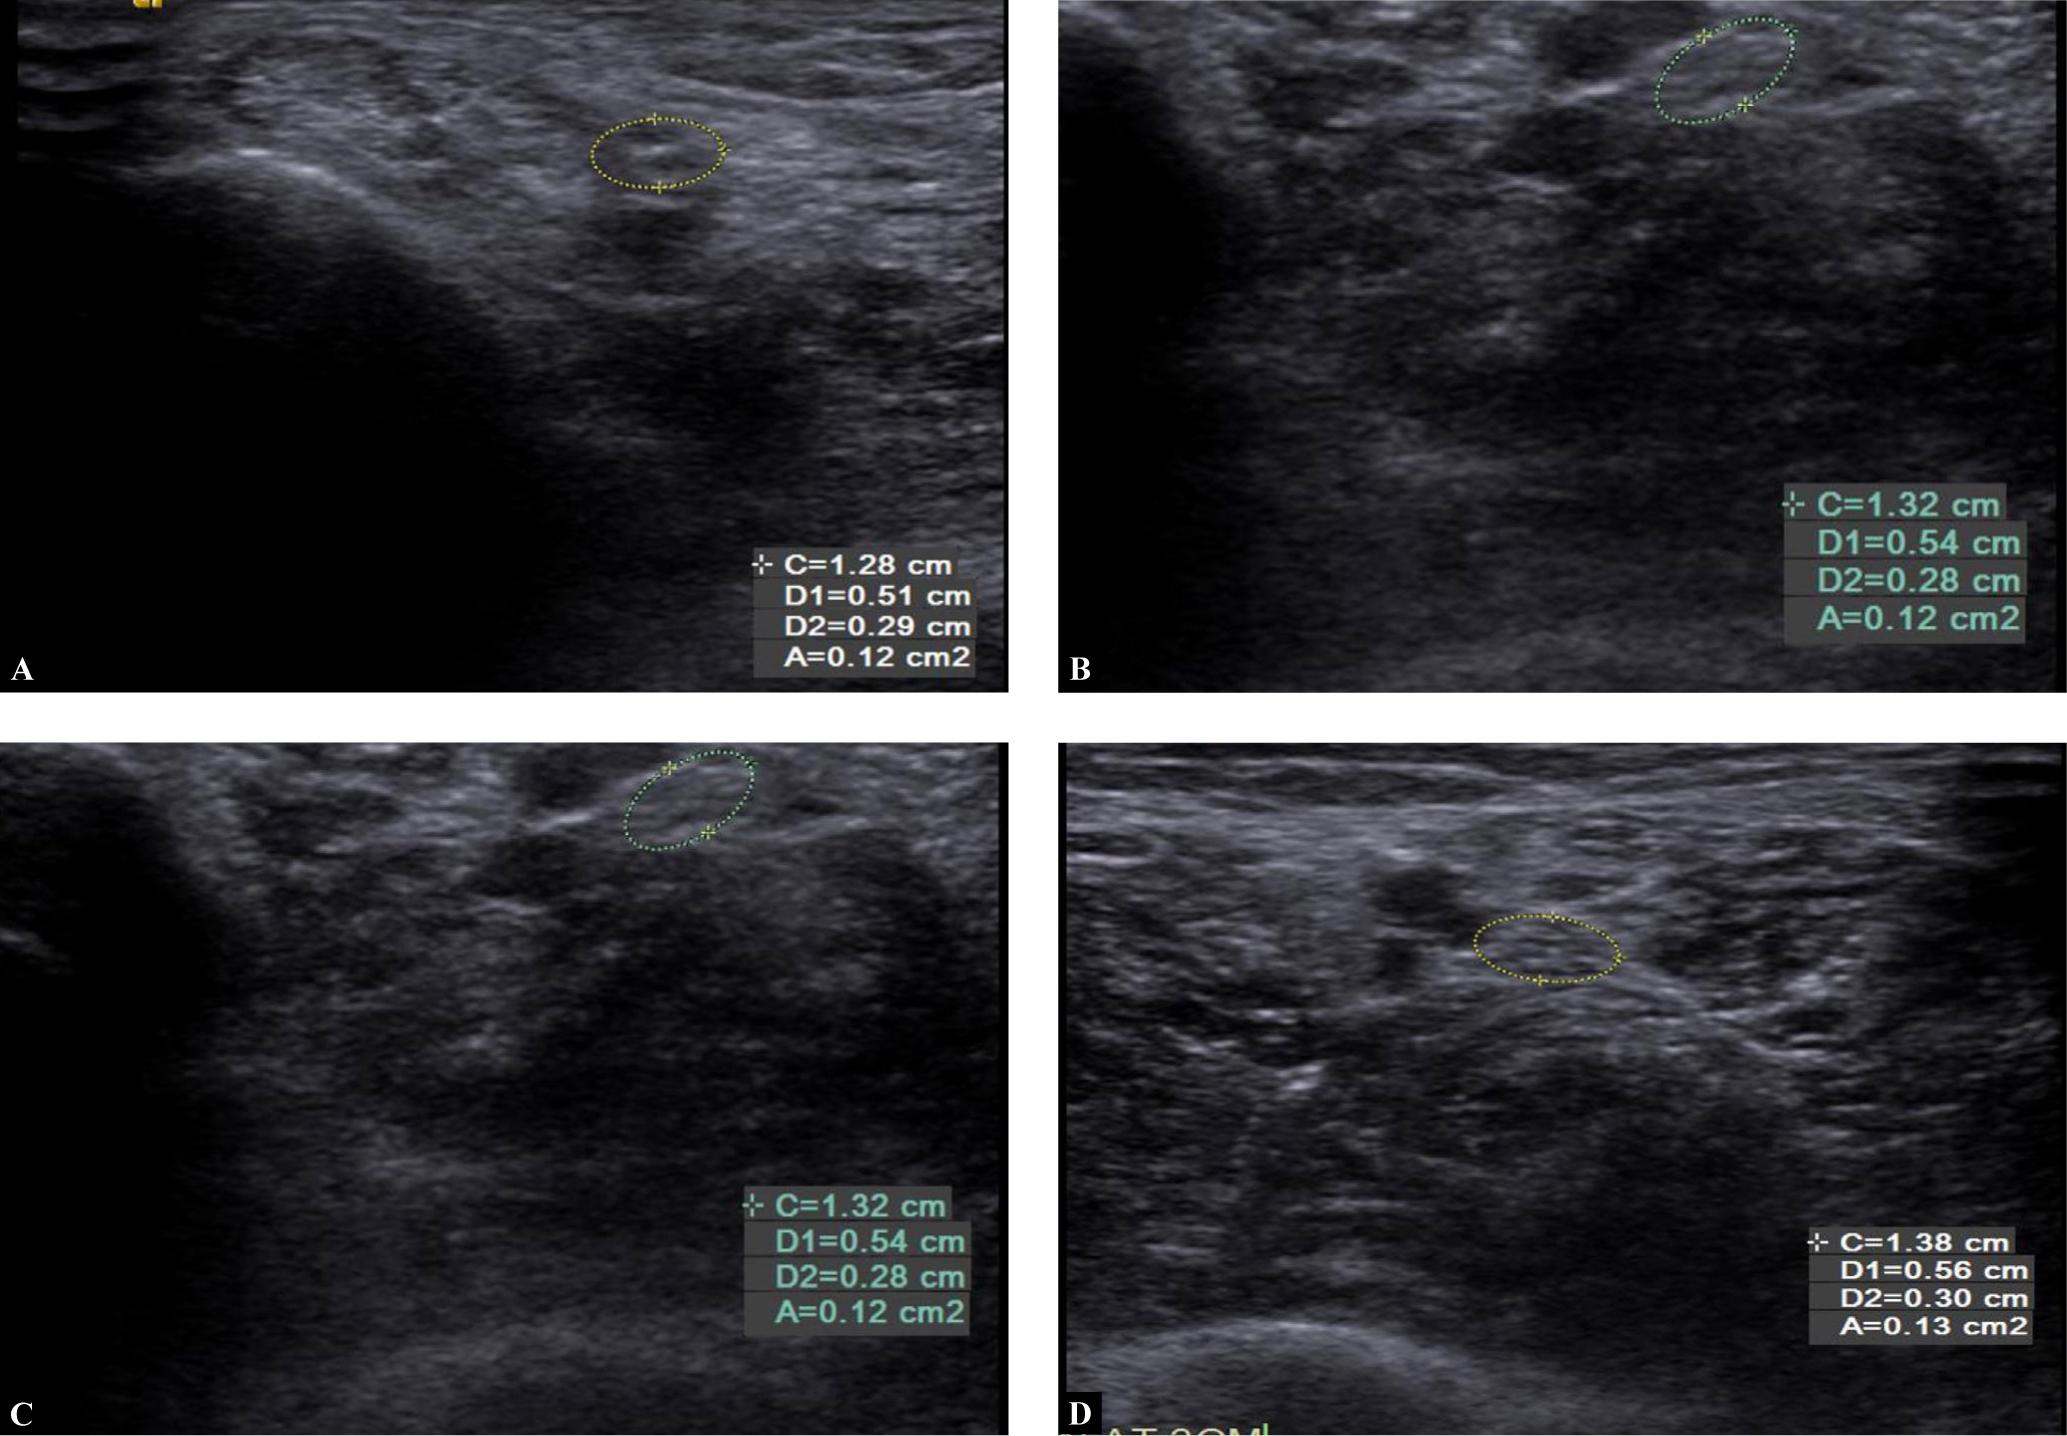

Fig. 2.

Transverse grey-scale ultrasound showing: A. Median nerve in a 45-year-old female patient diagnosed with T2DM 3 years previously. The patient did not have any neuropathic symptoms. Her HbA1c was 7.9% and her random blood sugar value was 250 mg/dl. It showed mean cross-sectional area of 8 mm2, meaning median nerve did not show any thickening. On monofilament examination, she was given a total score of 6 and her tactile sensations were intact. B. Thickening of tibial nerve (in the same patient) at 1 cm proximal to medial malleolus. C. Thickening of tibial nerve (in the same patient) at 3 cm proximal to medial malleolus. D. Thickening of tibial nerve (in the same patient) at 5 cm proximal to medial malleolus

We measured the CSA of the median nerve at 5 cm proximal to the wrist (MN 5 cm) and the tibial nerve at 1, 3 and 5 cm (TN 1 cm, TN 3 cm, TN 5 cm) proximal to the medial malleolus, revealing a positive relationship between the duration of diabetes and the CSA of these nerves, i.e. as the duration of diabetes increased, the nerve thickness also increased. There was a positive correlation between the CSA of the two nerves and HbA1c levels, duration of diabetes, RBS levels, and monofilament examination (Fig. 1A–1D). Subjects who had good glycaemic control and a shorter duration of diabetes showed no significant thickening of the nerves (Fig. 2A–2D).